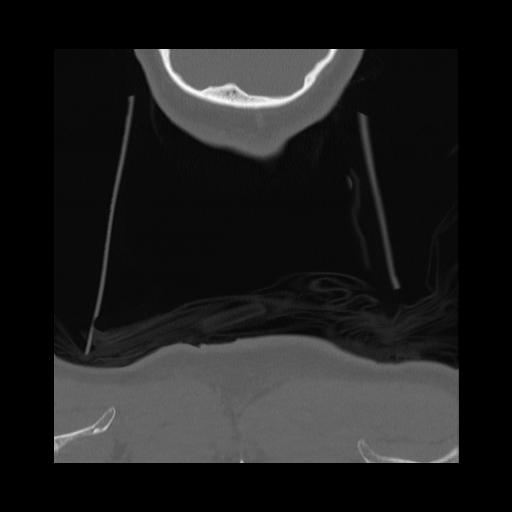

16 HUESO,,Coronal,2.000,HUESO,Coronal,